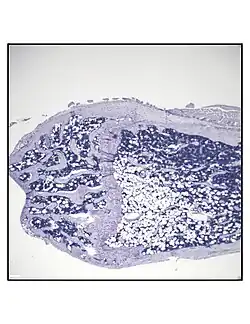

In order to understand the physiology of BMAT, various analytic methods have been applied. BMAds are difficult to isolate and quantify because they are interspersed with bony and hematopoietic elements. Until recently, qualitative measurements of BMAT have relied on bone histology,[51][52] which is subject to site selection bias and cannot adequately quantify the volume of fat in the marrow. Nevertheless, histological techniques and fixation make possible visualization of BMAT, quantification of BMAd size, and BMAT's association with the surrounding endosteum, milieu of cells, and secreted factors.[53][54][55]

Representative distal femur histologic section of a 16-week-old healthy C57BL/6 mouse demonstrating a typical quantity of marrow adipocytes. -